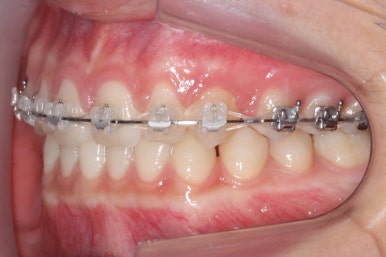

마무리 때의 사진입니다.

윗니만 부분교정하였지만 교합에도 이상 없이 매복되었던 송곳니는 매우 잘 위치를 잡았습니다.

송곳니 부위는 다시 틀어지지 않게 하기 위해 유지철사를 붙여주었습니다.

총 치료기간은 20개월 소요 되었습니다.